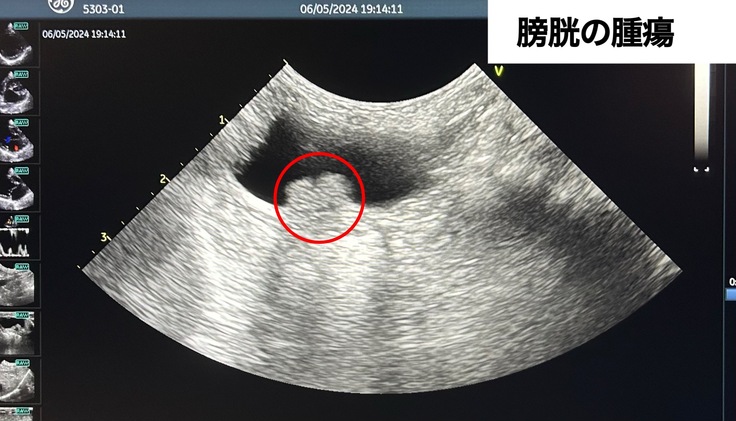

という診断になりました。その際、膀胱に大きな腫瘍も見つかりました。腫瘍が悪性だった場合余命3ヶ月と診断されましたが、検査結果では60%の確率で悪性ではないことがわかりましたが、細胞診では100%の判別ができないそうでとても心配です。

〈エコー〉